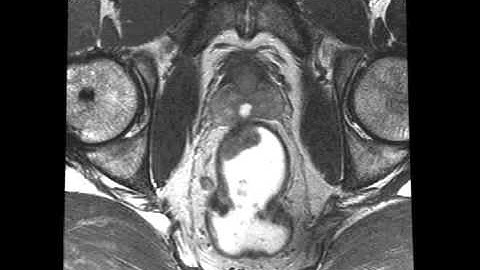

The Automatic Segmentation of Rectal Cancer on MRIs using nnU-Net